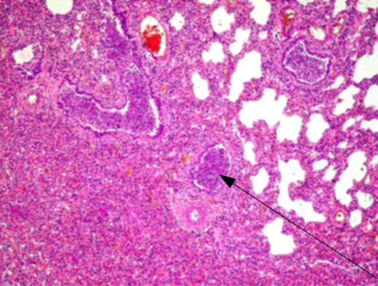

Identify Lesion

What is the cause?

Bronchopneumonia

Caused by infection of air way (trachea, bronchi)

Streptococci, staphylococci